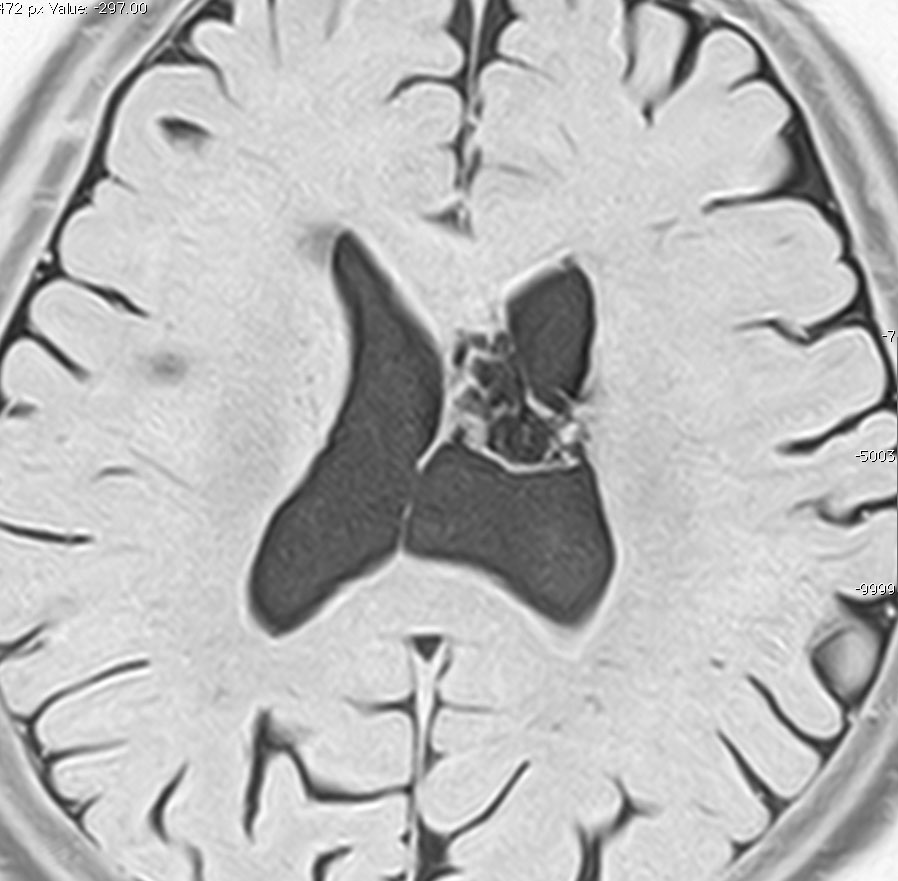

無症状の若い女性に偶然発見された例

central neurocytomaは腫瘍実質部分が多いものです。しかし,この例のように腫瘍の大部分をのう胞が占める症例もあります。

anterior transcallosal apprroachで亜全摘出しました。20代の女性でしたが,その後,子どもも生まれて元気です。

腫瘍の位置から,透明中核が発生母地であることが推測されます。central neurocytomaは,惻脳室壁にべとべとくっつくので,脳質上衣からの剥離は簡単ではありません。鑑別しなければならないのが,成人の毛様細胞性星細胞腫ですが,この症例では決定的な鑑別点はないでしょう。のう胞性の毛様細胞性星細胞腫と同様に,腫瘍の増殖力は低く無理して全摘出するものではありません。